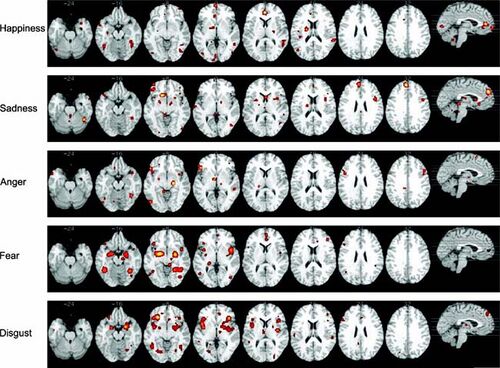

Some argue for a categorical approach, stipulating that happiness is one of a number of basic emotions, namely, anger, sadness, happiness, fear, and disgust.[3] Basic emotion theorists take these discrete emotions to be innate, universal, and to have unique physiological patterns, facial expressions, and neural correlates.[4] In other words, happiness should exist and be measurable in the brain distinct from the other basic emotions.

A recent meta-analysis by Vytal and Hamann (2010) provide some support for this approach to emotion research. In their analysis of 83 PET and FMRI neuroimaging studies from 1993 to 2008 with activation likelihood estimation, the researchers found that each of the five basic emotions was associated with a consistent and discrete set of neural correlates with regional brain activations.[5]